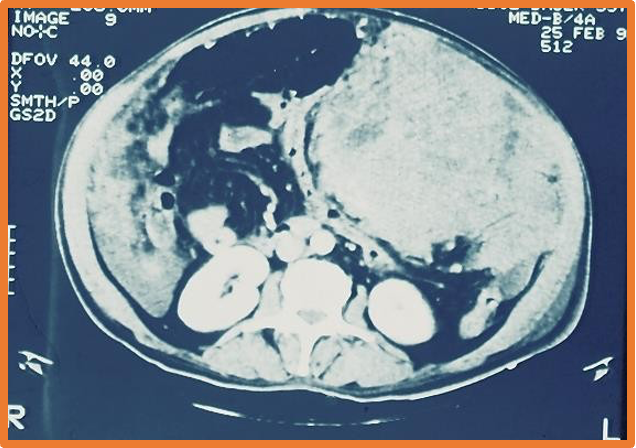

Pseudomyxoma peritonei:

- Rare, commoner in female due to ruptured mucinous cystadenocarcinoma (appendiceal origin in most cases).

- Abdominal distended due to yellow jelly like fluid.

- U/S, CT- scalloped indentation help diagnosis.

- Treatment: Excision of primary, debulking, chemotherapy.

- Recur over months to years